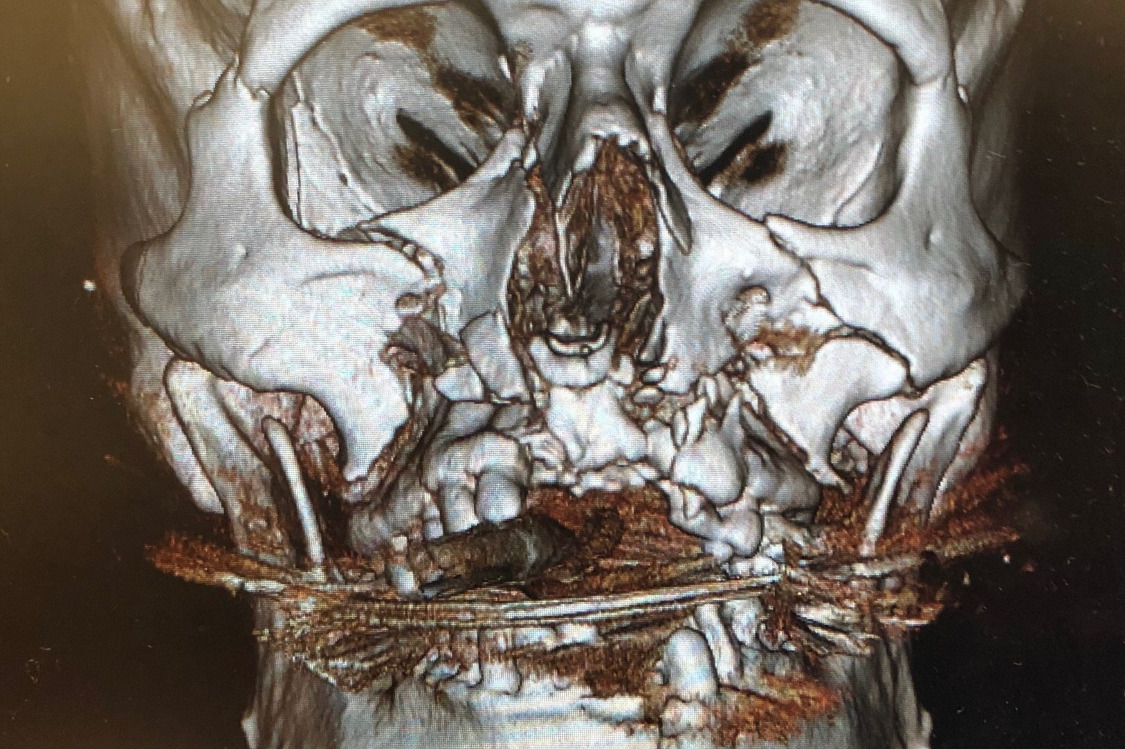

This is where I found him the following morning. He was intubated, had IV fluids galore, drainage tubes, a neck brace, etc. Since he took a majority of the impact to his face, the swelling was extreme. He struggled to even open his eyes and look at us.

That evening, he went back for a 6-7 hour surgery. Here is a list that one of the nurses gave me that lists all of the bones that were broken. Little did we know, but this was just the beginning. Currently, he is still awaiting a bone grant surgery and dental implants. Ruled as cosmetic and a surgery that will NOT be covered by insurance. It comes to a total of approximately $32,000 for the upcoming surgery alone.

This is where I found him the following morning. He was intubated, had IV fluids galore, drainage tubes, a neck brace, etc. Since he took a majority of the impact to his face, the swelling was extreme. He struggled to even open his eyes and look at us.

That evening, he went back for a 6-7 hour surgery. Here is a list that one of the nurses gave me that lists all of the bones that were broken. Little did we know, but this was just the beginning. Currently, he is still awaiting a bone grant surgery and dental implants. Ruled as cosmetic and a surgery that will NOT be covered by insurance. It comes to a total of approximately $32,000 for the upcoming surgery alone.